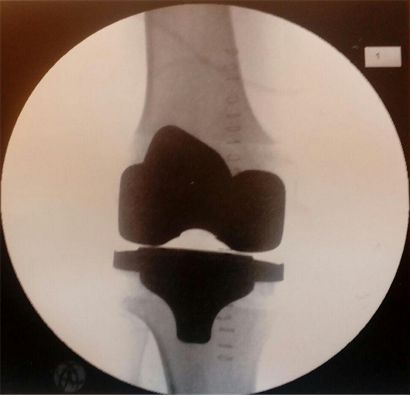

Die Schmerzen hielten sich noch in erträglichen Grenzen. Und je später operiert wird, denn eine Operation war unerlässlich, je länger hält dann das ‚neue‘ Knie. Anfang des letzten Jahres entschloss ich mich dann aber doch zu einer Voruntersuchung im Krankenhaus Buchholz. Eigentlich sollte das Knie in Hamburg operiert werden, aber Buchholz liegt für mich gewissermaßen gleich ‚um die Ecke‘. Und zumindest vom noch ziemlich neuen Chefarzt des Buchholzer Krankenhauses hatte ich viel Gute gehört. Am Freitag, den 13. April 2018 war es dann soweit: Mir wurde eine zementiertes Triathlon-Knie-TEP (Totalendoprothese) implantiert – also ein künstliches Kniegelenk eingesetzt. Dabei wurden bei mir alle Gelenkanteile überkront. Die wichtigsten Bänder des Kniegelenkes blieben erhalten und gewährleisten so das korrekte Gelenkspiel. Diese moderne Prothese erlaubt besonders viel Beugung bei größtmöglichem Knochenerhalt. Der Knochenverlust ist durch die Überkronung der Gelenkflächen minimiert. Die Operation verlief ohne Komplikationen und wurde vom besagten Chefarzt der Abteilung Orthopädie und Unfallchirurgie, Herrn Prof. Dr. C.H. Flamme, höchst persönlich durchgeführt. Bei der Chefarztvisite brachte mir der Doktor dann auch gleich ein Bildchen meines neuen Knies mit:

Willis neues Kniegelenk (rechts)